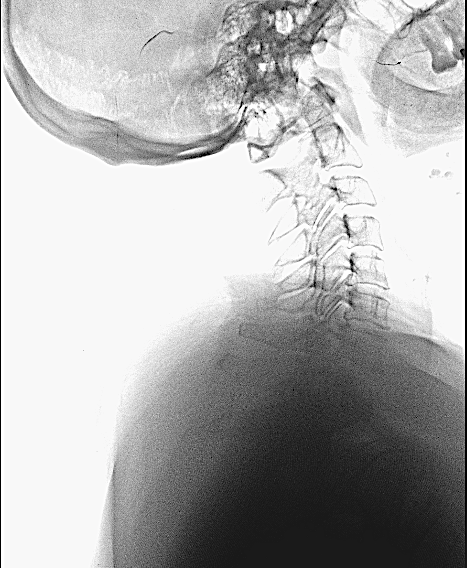

Control de 2 meses

Control 2 meses

Difícilmente se aprecia la prótesis

Copia con marcaje de los tornillos de la misma

En las RX lateral de control no se aprecia bien la caja atornillada, sin embargo, la paciente mejoró la clínica álgica y mostró recuperación funcional en MSD en los controles, por lo que decidí esperar a los 6 meses para la RM cervical.